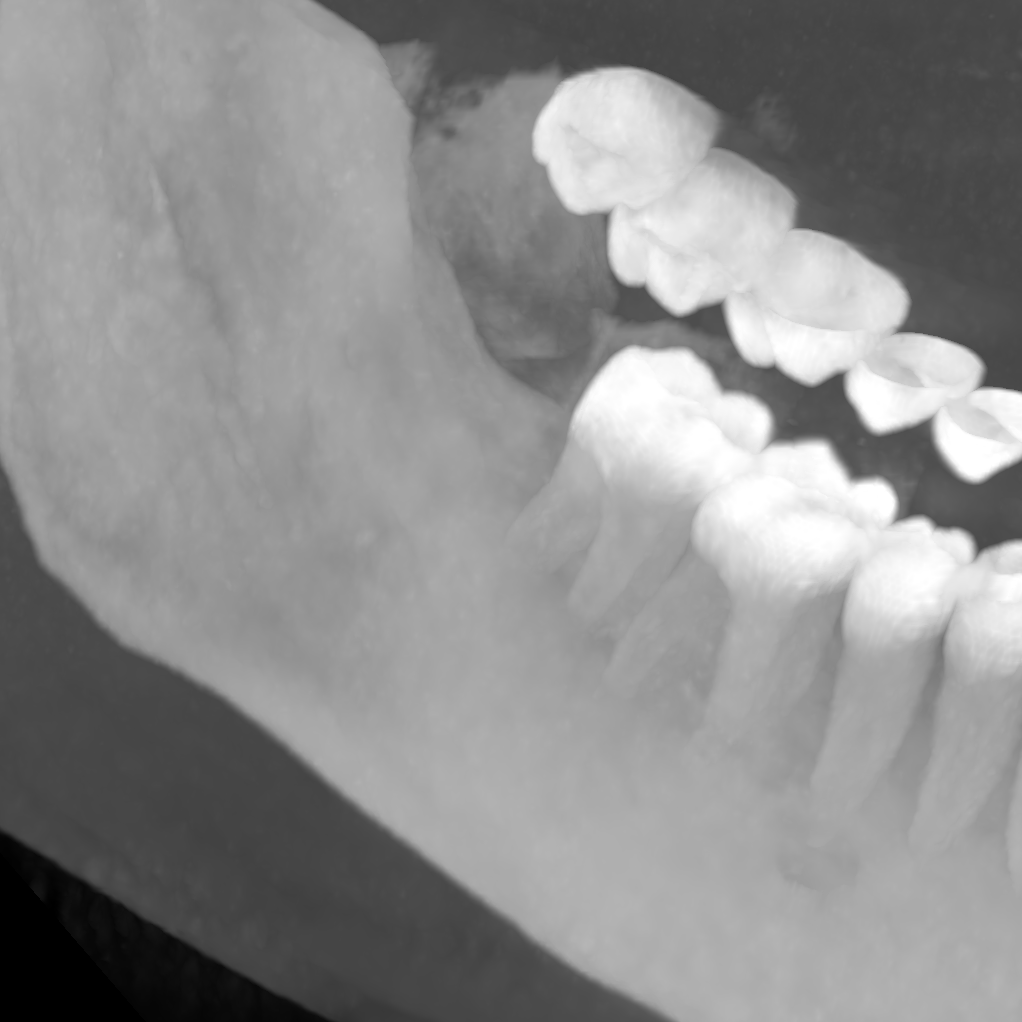

| ToothFairy[6, 5] | 3D | binary | 138 | Inferior Alveolar Canal |

We employ five public datasets featuring thin structures for validating the proposed Skeleton Recall Loss. The datasets span natural as well as medical images, covering a range of segmentation challenges, including both binary and multi-class segmentation problems in 2D as well as 3D contexts. An overview of the datasets can be found in Tab. 1. Among the three 2D datasets used in this study, the Digital Retinal Images for Vessel Extraction (DRIVE) dataset [32] was employed, focusing on retinal vessel segmentation. Additionally, structural inspection images designed for concrete crack segmentation (Cracks) [36] and aerial images of Massachusetts for road segmentation (Roads) [21] were included, highlighting the diversity of thin structures in natural and constructed environments. In the 3D domain, we incorporated two cutting-edge medical image segmentation challenge datasets. One of them was ToothFairy111https://toothfairy.grand-challenge.org/, which was a segmentation challenge on 3D Cone-Beam CTs [6, 5] featuring the inferior alveolar canal as the target structure. Additionally, the TopCoW222https://topcow23.grand-challenge.org/ dataset for topology-aware 3D segmentation of vessels in the Circle of Willis for CTA and MRA data [40] was utilized, encompassing binary as well as multi-class segmentation on 13 different subtypes of vessels. This diverse set of datasets enables a comprehensive evaluation of the proposed Skeleton Recall Loss, demonstrating generalizability of the method to a wide range of thin structure segmentation challenges in both 2D and 3D contexts.